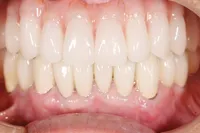

■治療前:上下顎 義歯での食事に満足されていない

■治療後:上下顎 複数本のインプラントを使い固定式で治療

| 主訴 | 現在義歯を使用しているが、しっかりと咬んでなんでもおいしく食事したい |

| 治療方法 | 上下顎 複数本のインプラントを使用しての治療 |

| 治療期間 | 約1年 |

| 通院回数等 | 約20回 |

| 費用 | 約600万円(税込) |

| リスク・副作用 | 術後の腫れ・痛み |